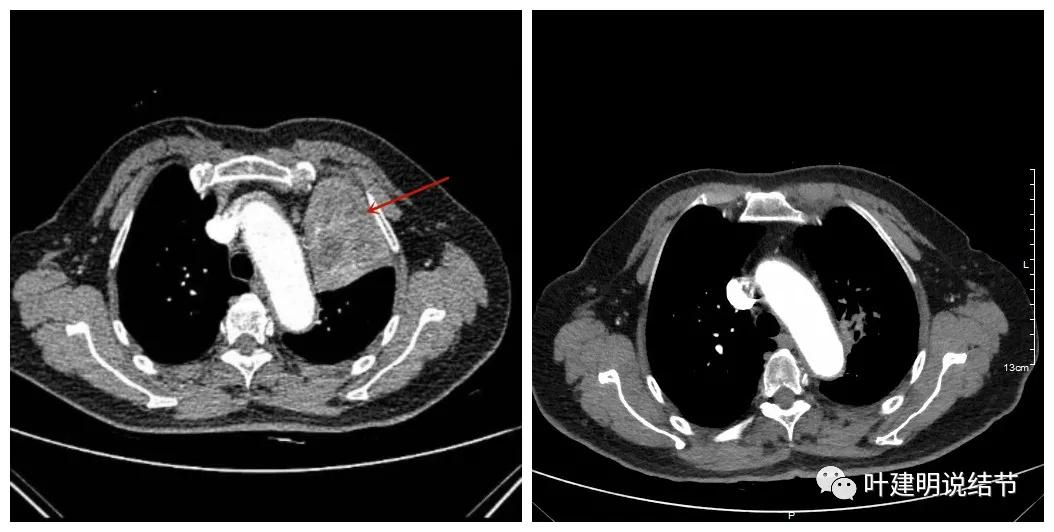

可见效果相当的好,如果我们把差不多同样层面的放到一起对比,更能显示化疗加免疫的惊人效果:

我样的治疗效果,显然超出了我们之前的预期,那么接下来拟选择行手术治疗,初定左上叶袖式肺叶切除加淋巴结清扫,但因为肺门区仍有软组织影,与肺动脉的关系仍密切,肿瘤与肺动脉间能否游离开来还是未知数,但至少得努力争取,鉴于患者年纪虽大,肺功能指标尚可,血气分析也基本正常,所以与患方沟通后确定行手术探查,但也也说明有万一全肺切除的可能(虽然这种可能性较小)。